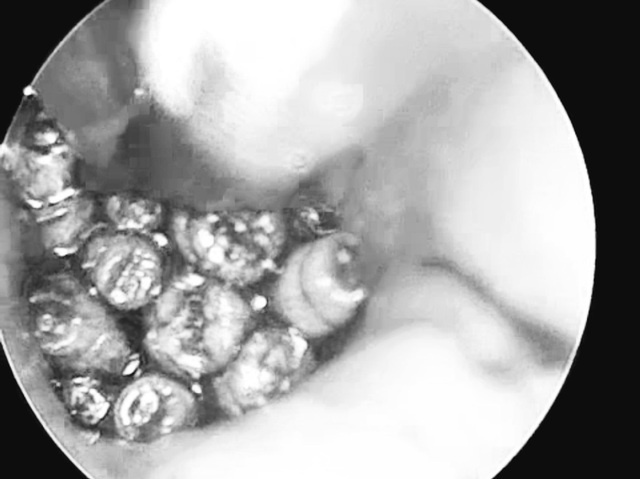

Qua nội soi, bác sĩ Bệnh viện Quảng Trị phát hiện ống tai bệnh nhân đọng nhiều máu tươi, bên trong có dị vật màu trắng giống con giòi lấp đầy màng nhĩ.